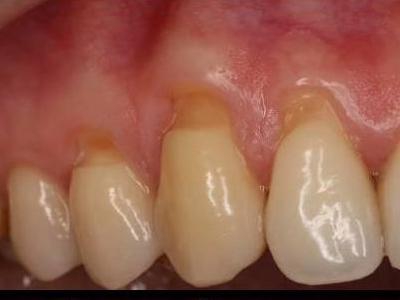

Опустились дёсны в нескольких местах, обнажились шейки зубов. Чувствительные, болят от прикосновений, могут реагировать на холодное, горячее, сладкое.

Ситуация как примерно на пик2.

Предлагали два варианта:

1) Пластика десны, когда кусок кожи с нёба отрезают и пришивают к десне, чтобы закрыть оголившийся участок

2) Простое заделывание чувствительных мест пломбой/аналогом пломбы без пластики дёсен.

В первом случае меня беспокоит, что будет, если на оголившемся участке зуба есть кариес (сейчас из-за общей более тёмной природной пигментации шеек зубов + налёта не понятно), и я зашью этот кариес под кожу? Кариес будет прогрессировать под десной?

А во втором случае, дохтур сказал, что к заделанным пломбой шейкам зубов десна уже назад не прирастёт, даже если пересадить, то есть пластика дёсен будет невозможна.